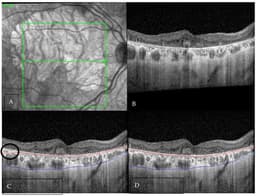

• Healthcare: Building upon prior initiatives like CancerLLM and MedQARo, 2026 has seen medical AI systems emphasizing factual accuracy, trustworthiness, and ethical compliance reach new heights. Noteworthy developments include advances such as deep learning-based choroidal boundary detection utilizing spectral-domain optical coherence tomography, which enhances diagnostic precision in ophthalmology. These innovations aim to minimize misdiagnoses, uphold patient rights, and are supported by standardized validation pipelines that ensure models meet rigorous medical standards before clinical deployment, thereby reducing potential harm.